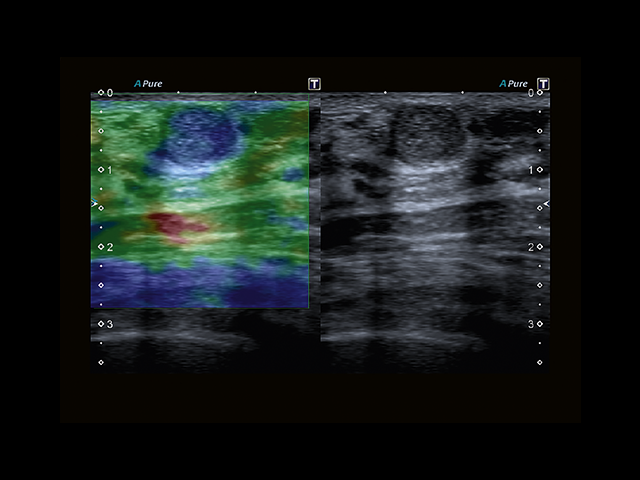

Обновленная версия легендарного УЗ-сканера. Стационарный аппарат экспертного класса Aplio 500 Toshiba NEW, визуализирует анатомические структуры в высоком разрешении. Модель позволяет выявить микрокальцификаты, новообразования, нарушения в работе сердца, сосудов и мышц. Присутствует функция виртуальной эндоскопии, 4D-сканирования, эластометрии тканей, УЗИ с контрастированием. За повышение качества изображения отвечают технологии ApliPure и Superb Microvascular Imaging. Первая задействует возможности пространственного и частотного кодирования, формирует цельный визуальный ряд с сохранением клинических маркеров. Вторая улучшает отображение микрососудистого русла, используя доплеровский эффект. Модель оснащена 21-дюймовым монитором, имеет 4 активных порта. Возможно подключение педиатрических, интраоперационных, лапароскопических и чреспищеводных датчиков.

- MicroPure. Высокотехнологичное решение в области выявления микрокальцификатов – маркеров новообразований злокачественного типа. Маркеры идентифицируются путем изучения затененных изображений целевого участка. Микрокальцификаты отображаются в виде белых пятен.

- SMI. Опция, упрощающая визуализацию микроциркуляторного русла. С ее помощью обследуются сосуды с низкой интенсивностью кровотока, изучаются наиболее тонкие структуры. SMI упрощает диагностику новообразований, минимизирует вероятность ошибки.